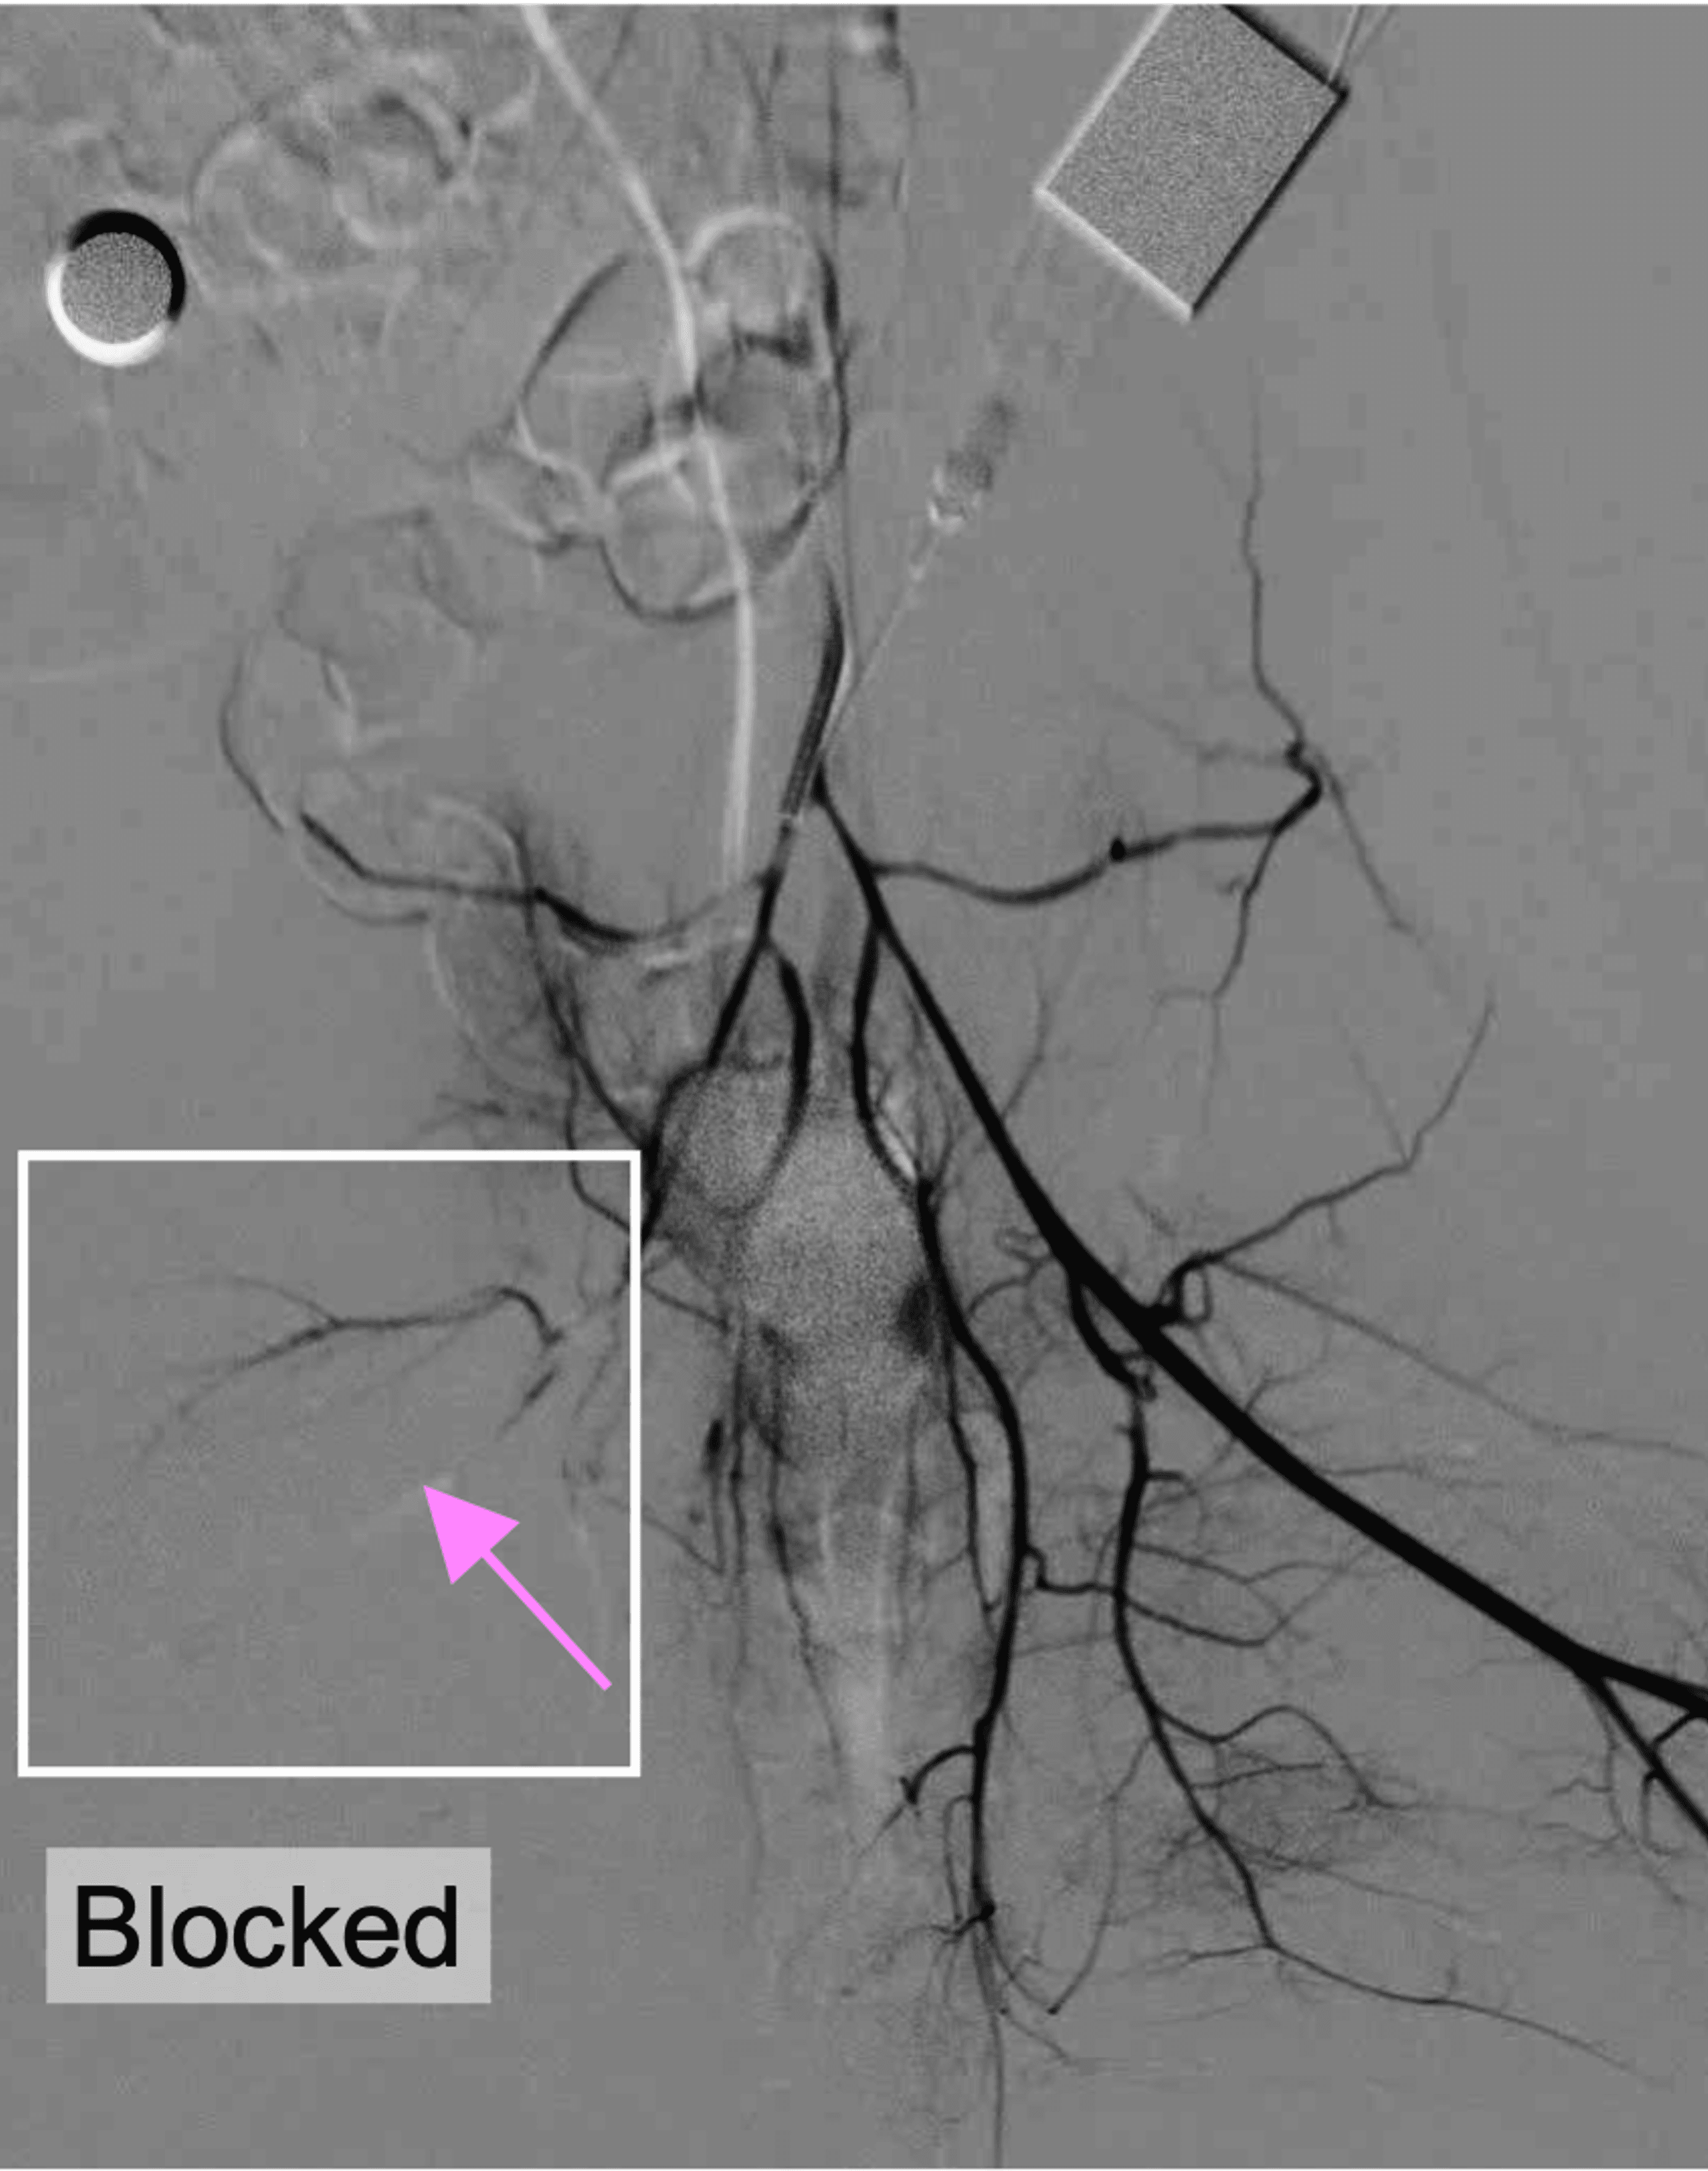

1 out of 2 heart attack patients still develops microvascular obstruction (MVO), blockage in the heart’s smallest blood vessels — even after timely treatment. MVO remains a major driver of poor recovery, heart failure, and long-term mortality after heart attack treatment.

SonoRobotics develops catheter-based ultrasound technology for thrombus disruption and microvascular protection in PCI workflows.